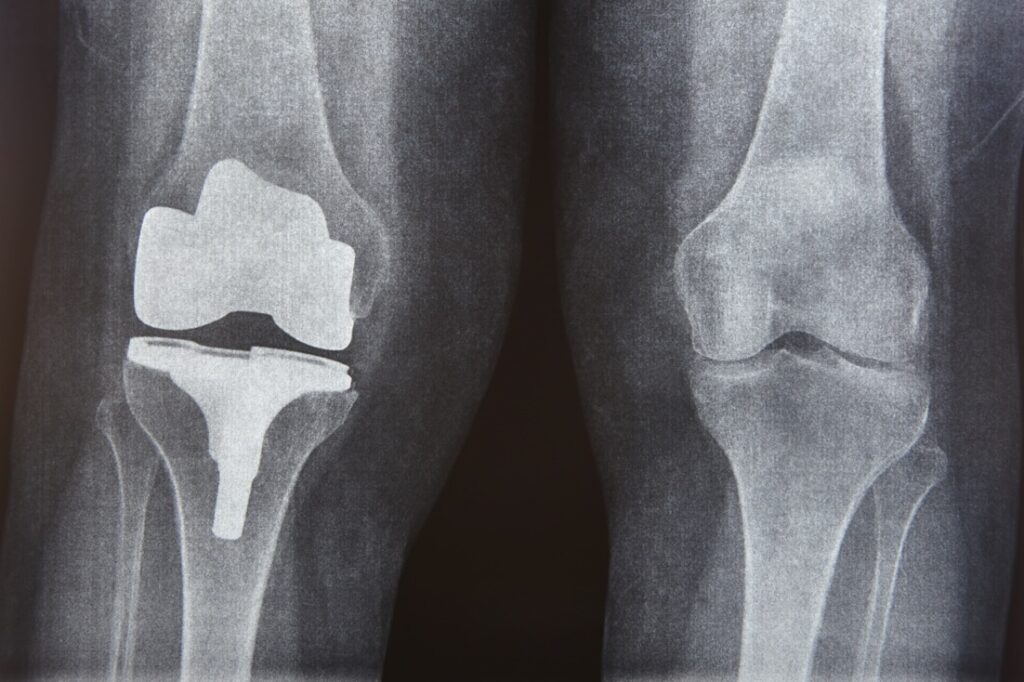

Una prótesis de rodilla es un procedimiento quirúrgico en el que se reemplazan las superficies articulares dañadas por componentes artificiales diseñados para restaurar la función de la articulación.

El objetivo principal es disminuir el dolor, mejorar la movilidad y permitir al paciente retomar actividades cotidianas con mayor comodidad. Los materiales utilizados están diseñados para ofrecer durabilidad y un movimiento lo más natural posible dentro de la articulación.

La indicación de una prótesis siempre se realiza después de una evaluación completa, considerando síntomas, estudios de imagen y expectativas del paciente.